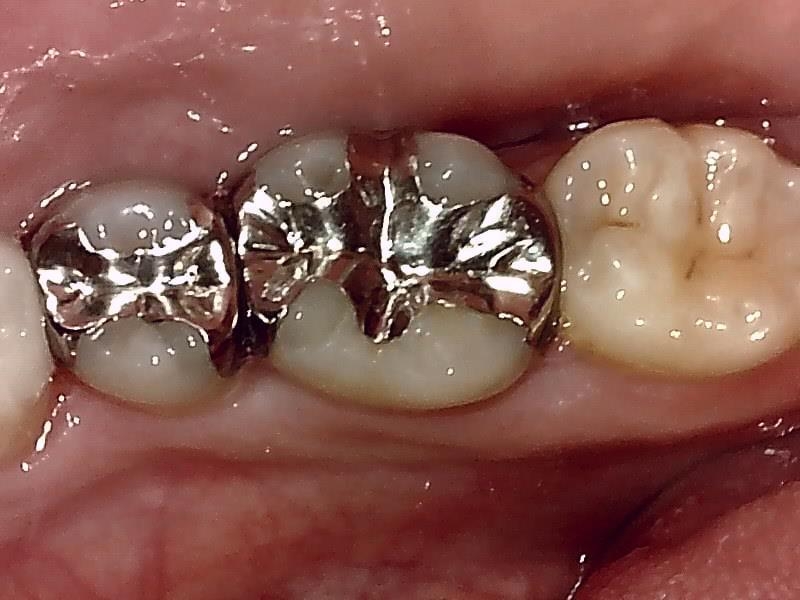

術前の咬合面の写真

不適合な金属の詰め物の除去。